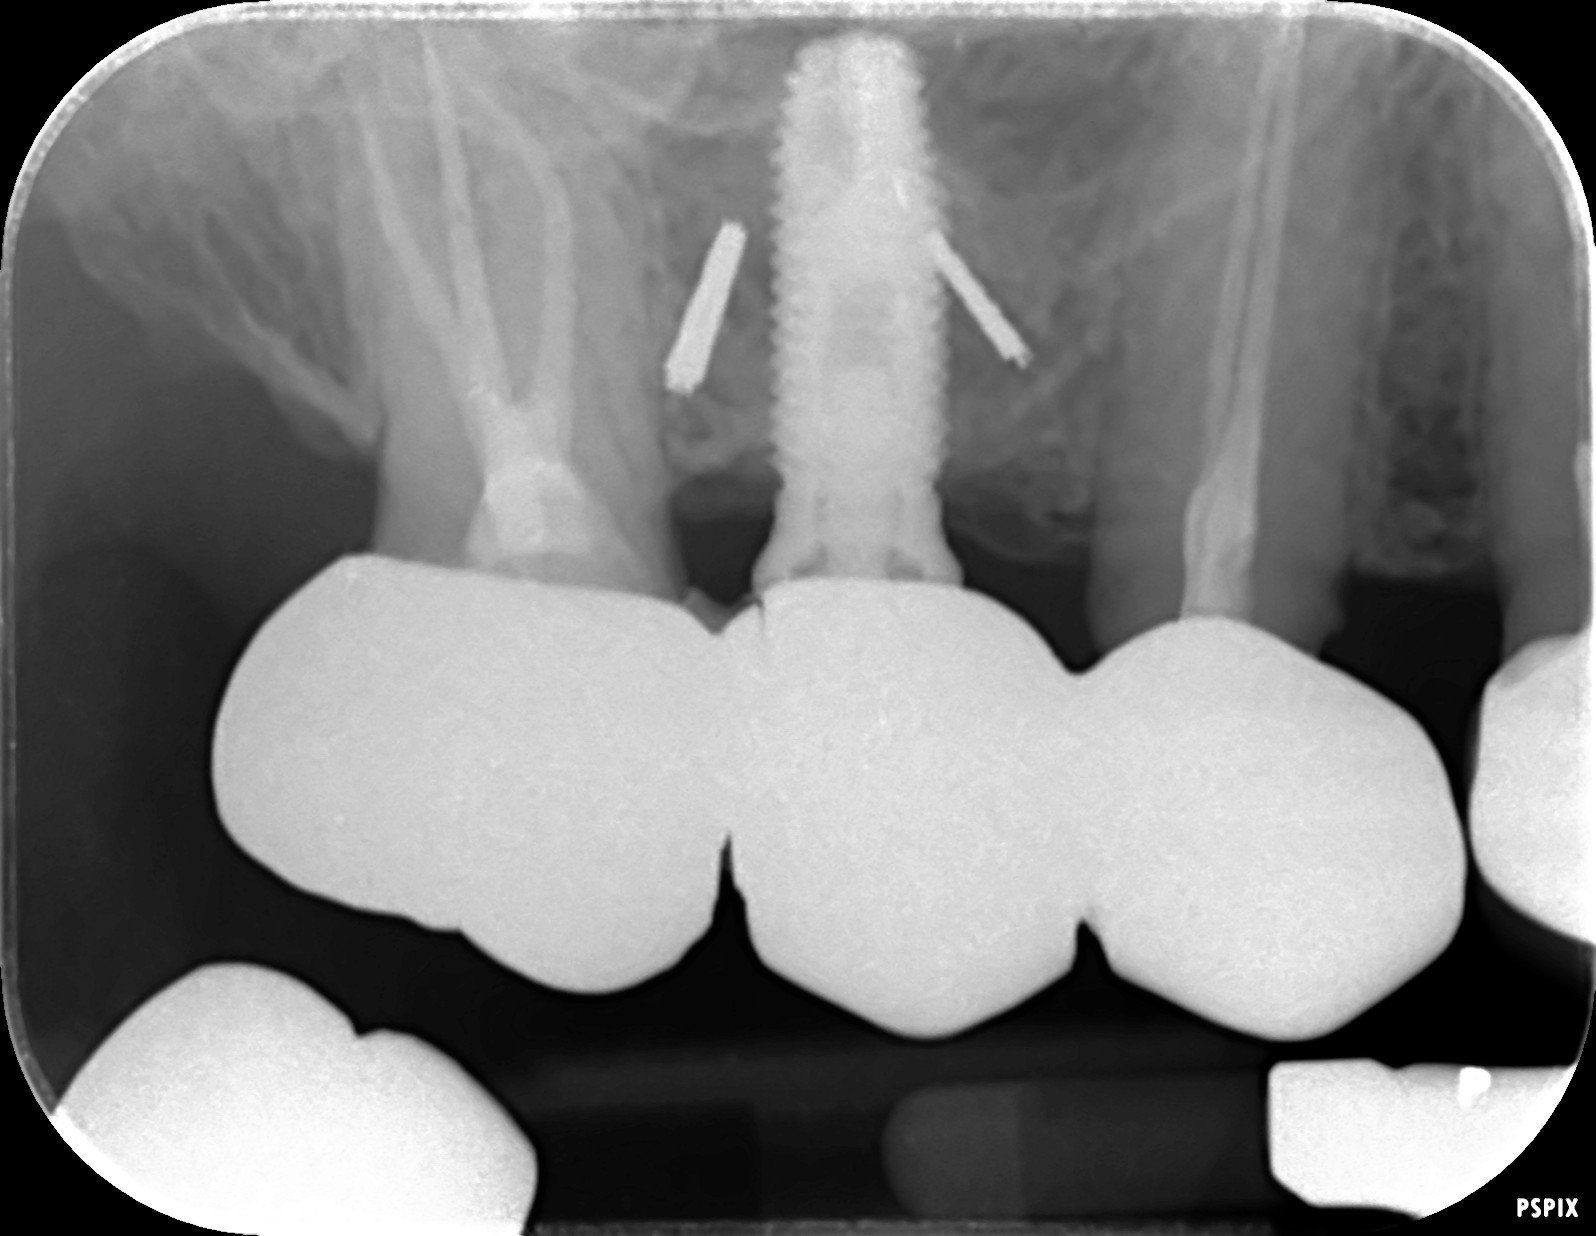

Buenas tardes compañeros, a ver si podéis ayudarme a identificar estos implantes Un saludo